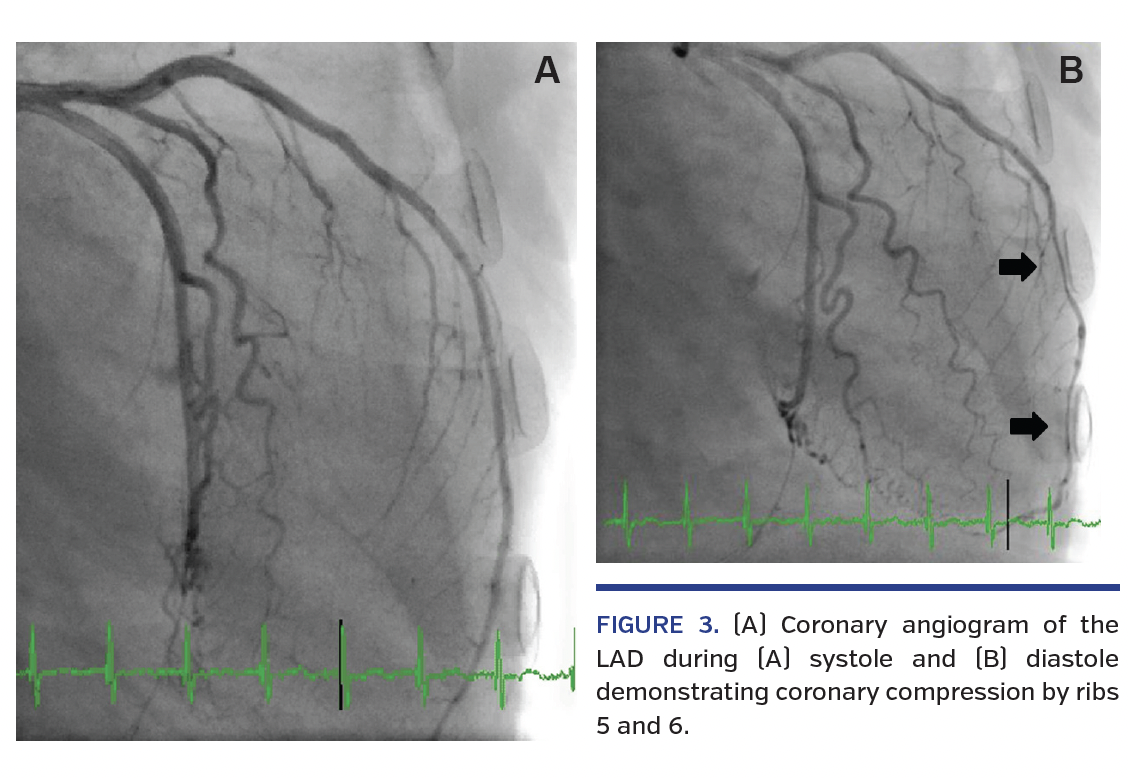

Cardiothoracic surgery consultation was obtained and the patient accepted for mitral and tricuspid valve surgery. Coronary angiogram was performed for presurgical evaluation. All major coronary arteries had mild luminal irregularities in a right dominant circulation; however, the mid left anterior descending artery was noted to have diastolic compression against the 5th and 6th ribs, secondary to lateral displacement of the LV from the severely enlarged left atrium (Figures 3A and 3B; Video 1).

The patient underwent mitral valve replacement with a bioprosthetic porcine valve, tricuspid valve annuloplasty, and left atrial appendage ligation with good result and an uncomplicated postoperative course. Extrinsic coronary compression is a rare finding and usually occurs in the setting of cardiac chamber remodeling or enlargement. There are no randomized data regarding appropriate therapy; however, correcting the underlying cause of chamber enlargement would be the first priority. In our case, the patient underwent mitral valve replacement for severe rheumatic mitral stenosis, which would optimistically allow for attenuation of left atrial size and relief of coronary compression. However, percutaneous coronary intervention has been reported as a treatment option as well. Herein, we describe a case of massive cardiac chamber enlargement with consequential diastolic compression of the LAD.